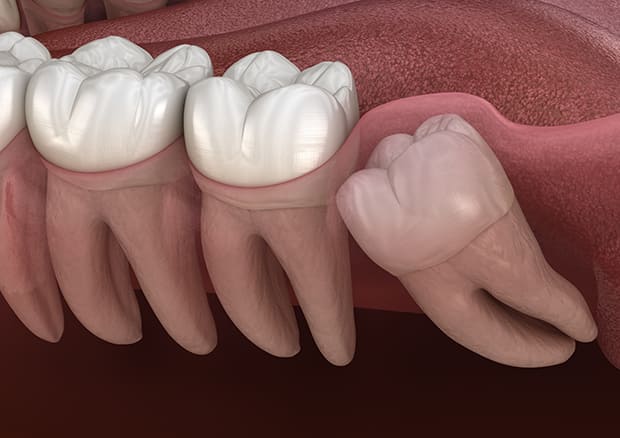

斜めに生えている親知らず

親知らずが斜めに生えて隣の歯にぶつかって圧迫してしまうタイプです。

このタイプが最も多いです。このタイプは虫歯になりやすいだけでなく、隣の歯を圧迫し、咬み合わせや歯並びに影響が出る場合もあるので抜歯をおすすめします。